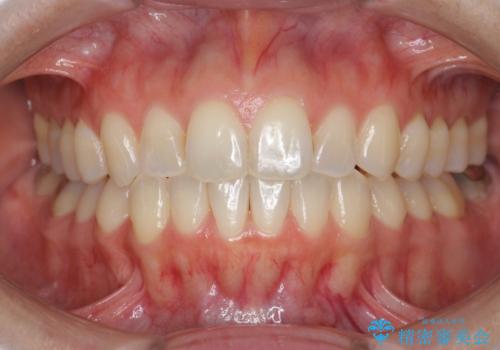

[ インビザライン矯正 ] マウスピースで治す前歯のがたつき

担当医 大元洋佑

![[ インビザライン矯正 ] マウスピースで治す前歯のがたつきの症例 治療前](https://seimitsushinbi.jp/wp/wp-content/uploads/2023/11/C7-500x350.jpg?v=1699665009)

![[ インビザライン矯正 ] マウスピースで治す前歯のがたつきの症例 治療後](https://seimitsushinbi.jp/wp/wp-content/uploads/2023/11/IMG_2993-500x350.jpg?v=1699664953)